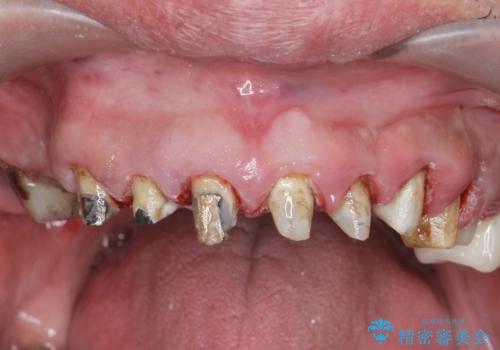

[ 歯周外科手術 ] セラミック治療後の歯ぐきの違和感

- 「セラミック治療を他院で受けたが、それ以来歯ぐきが腫れ違和感がある、改善してほしい。」と歯ぐきの状態改善を希望され来院されました。

歯周組織検査を行うと歯ぐきからは容易に出血し、X線検査より歯とセラミッククラウンの適合が悪い(ピッタリと合っていない)状態が示唆され、歯ぐきの炎症を惹起している状態でした。

セラミッククラウンを除去し仮歯を装着し、歯周外科手術を行い歯ぐきの状態を改善したのち、適合の良いセラミッククラウンを再作製をする治療計画としました。